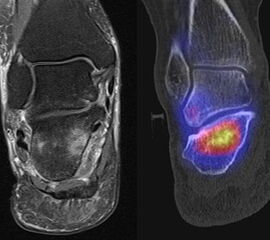

Abbildung 2.1.

Bildbeispiele symptomatische OCL

Zum Lesen der Bildbeschreibung und zur Vollansicht bitte das Bild anklicken. Bild: H. C. Rischke